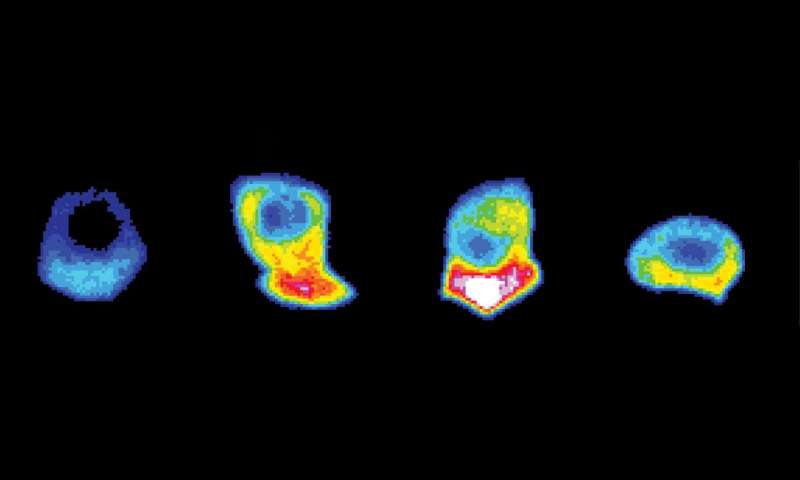

加德展示了一个入侵细胞的延时拍摄,当它推进并楔入邻近的组织。这种细胞被设计了一个传感器,当一种叫做ATp的携带能量的分子达到一定水平时,它就会发光,就像细胞燃料计一样。就在细胞即将突破的时候,细胞前线后面出现了一束光,显示出在突破时大量的ATp。

研究人员表示,这种ATp是由一种叫做线粒体的细胞器产生的,线粒体是细胞的能量工厂,它被一种叫做netrin的分子线索引导到细胞的入侵前线。

当研究人员使这些基因失活时,葡萄糖和ATp水平下降,线虫细胞停止了它们的传播。通过显微镜,他们可以看到细胞在微弱地伸出新的活塞状突起,想要通过,但大多数细胞都被推迟了,三分之一的细胞完全停止了前进。